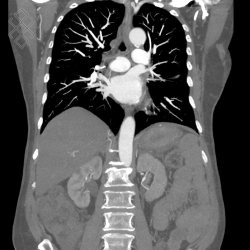

Scanner Thoraco-abdomino-pelvien